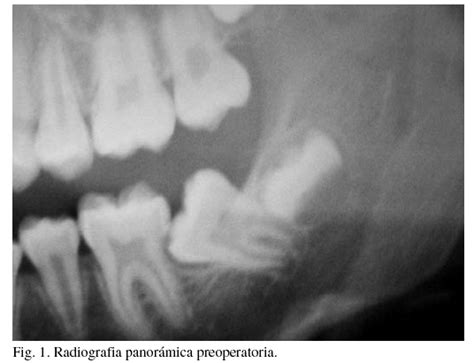

- Radiografía y diagnóstico: El primer paso de una endodoncia es realizar una radiografía que ayudará a valorar la posible afectación de la pulpa o del nervio del diente.

Se presenta el caso de una joven de 16 años de edad con episodios recurrentes de dolor espontáneo en la región de los segundos molares inferiores. El examen clínico intraoral mostró que los dientes habían erupcionado parcialmente aunque se encontraban por debajo del plano oclusal, debido a una acusada inclinación mesial e impactación en la superficie distal de los primeros molares.

El plan inicial de tratamiento se basó en resolver la fase aguda de pericoronaritis y establecer después un seguimiento de 5 meses. Después de este período, el examen clínico y radiográfico reveló la progresión del desarrollo radicular pero no se observó mejoría en la posición de los segundos molares. Se tomó la decisión de enderezar los dientes impactados mediante la colocación de anillos elásticos separadores de ortodoncia entre los molares para redirigir la erupción dentaria.